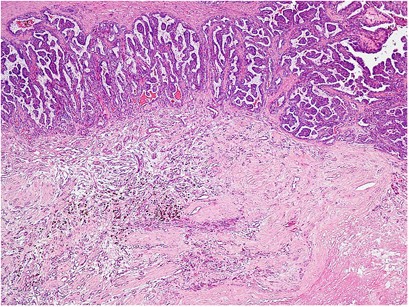

Gross photographs of 13 tumors were available for review. At the gross level, the tumors were variably cystic (Table 1), some with a multilocular cystic appearance and focally small solid nodules within the tumor septa or at the junction with the renal parenchyma (Figures 1a and b). Other tumors showed a partially solid white-tan, pale yellow or red-brown, congested cut surface. In tumors with a significant solid component, the cysts were often arranged at the periphery of the solid areas, with a distinctive angulated, flattened, or irregular contour of the cysts. Grossly evident areas of necrosis or venous or renal sinus invasion were not present in any tumor. Although solid areas were often white-tan to pale yellow, none of the available gross photographs revealed the characteristic bright yellow, fleshy, and heterogeneous cut surface that is typical of clear cell renal cell carcinoma. Microscopically, papillary architecture was present at least focally in all tumors. However, 19 tumors (35%) included only rare, blunt or rounded, minute papillae (Figure 1c). Twenty-eight tumors (51%) showed foci of more prominent branching papillae and eight (14%) showed a majority of papillary architecture or large areas ( × 10 magnification fields) composed entirely of branched papillae. In 29% of tumors, the papillary structures showed a distinctive architectural pattern, composed of a thick, rounded, main papillary core with a hypocellular fibrovascular stroma, giving rise to multiple smaller similar-appearing rounded secondary papillae (Figure 1d). Other tumors showed a pattern of ‘glomeruloid’ papillae (Figures 2a and b), with small, blunt papillary structures protruding into small glandular spaces rather than large cysts. One tumor showed patchy areas with eosinophilic cytoplasm, corresponding to the only areas of Fuhrman nuclear grade 3 in any of the lesions (Figure 3a). Neither foamy macrophages within papillae nor psammoma bodies were present in any tumor.

(a) Gross appearance of a multilocular cystic tumor with focal rounded, solid nodules at the periphery of the lesion. (b) Low magnification appearance of the same tumor, confirming the presence of mixed solid and cystic components. (c) A predominantly cystic tumor with only minute, rounded/blunt papillae protruding into the cystic spaces. (d) Another tumor with characteristic branching papillae showing thick, rounded papillary cores with hypocellular fibrovascular stroma, giving rise to smaller rounded, secondary papillae.

The majority of tumors (47) showed areas of branched or stellate tubular structures, similar in shape to benign prostatic acini (Figure 3b), showing a ‘garland’ or ribbon-like layering configuration around hyalinized or fibrous zones (Figure 4) in 5 tumors (9%). Branched tubular structures were lacking only in eight tumors that were >75% cystic, differentiated from multilocular cystic renal cell carcinoma on the basis of variably prominent papillae and other solid tumor nodules. The majority of tumors (82%) showed at least focal areas of a dense, compact arrangement of tubular structures, similar to or indistinguishable from those of clear cell renal cell carcinoma (Figure 5a). Twenty-four tumors (44%) showed at least the focal presence of cells with nuclei aligned at the apical end of the cells, similar in appearance to early secretory phase endometrium, or ‘secretory cells’1 (Figure 5b).

(a) Areas of compact and acinar growth, histologically indistinguishable from clear cell renal cell carcinoma. (b) ‘Secretory’ cells, with nuclei aligned above the basement membrane, similar to the subnuclear vacuoles of early secretory pattern endometrium. (c) Peripherally located cysts at the interface between the compact and acinar areas of the tumor and the uninvolved renal parenchyma. (d) Focal solid nodules, composed of branched acinar structures in an extensively cystic tumor, showing diffuse positivity for cytokeratin 7 (e) and carbonic anhydrase IX (F). Staining for CD10 (g) is limited to the cystic component, showing (h) positive apical membranous staining in the lining cells only.

Almost all of the tumors (98%) included a cystic component, usually comprising greater than half of the tumor volume (median cystic component comprising 75%), though a minority of tumors showed only small microcystic structures (Table 1). In tumors with a significant solid component, the cysts were often arranged at the periphery of the lesion (Figure 5c). Some tumors showed a predominantly cystic architecture, mimicking multilocular cystic renal cell carcinoma, with only focal rounded papillae protruding into the cystic spaces or small solid nodules composed of branched ducts (Figure 5d). In some tumors, the solid nodules were within the septa and in others at the outer edge of the tumor, adjacent to the renal parenchyma. All tumors were at least partially pseudo-encapsulated, with typically a fibrous capsule. Ten tumors showed calcification, of which four showed ossification. A few areas of ossification included fatty bone marrow.